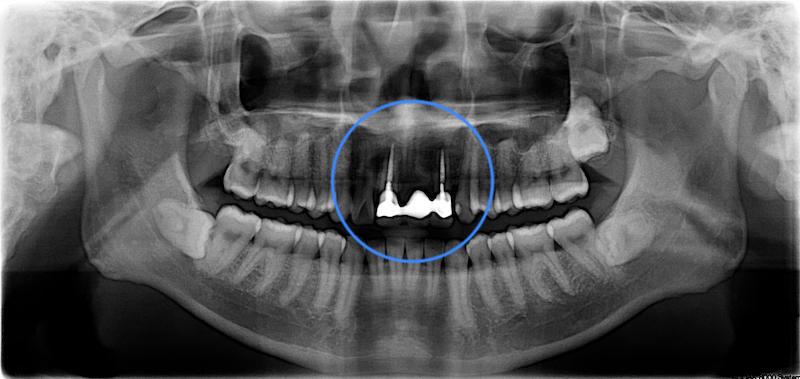

治療前 X 光片,假牙尚未拆除

從口內和 X 光片的檢查發現,Mr.Wang 的全口牙周的狀況還算健康,大部分的牙周齒槽骨流失不到 15 %,但是還剩下三顆阻生智齒,右上第二大臼齒的後方也有局部的嚴重牙周病。牙周相關的診斷是:全口輕度、局部嚴重慢性牙周病。